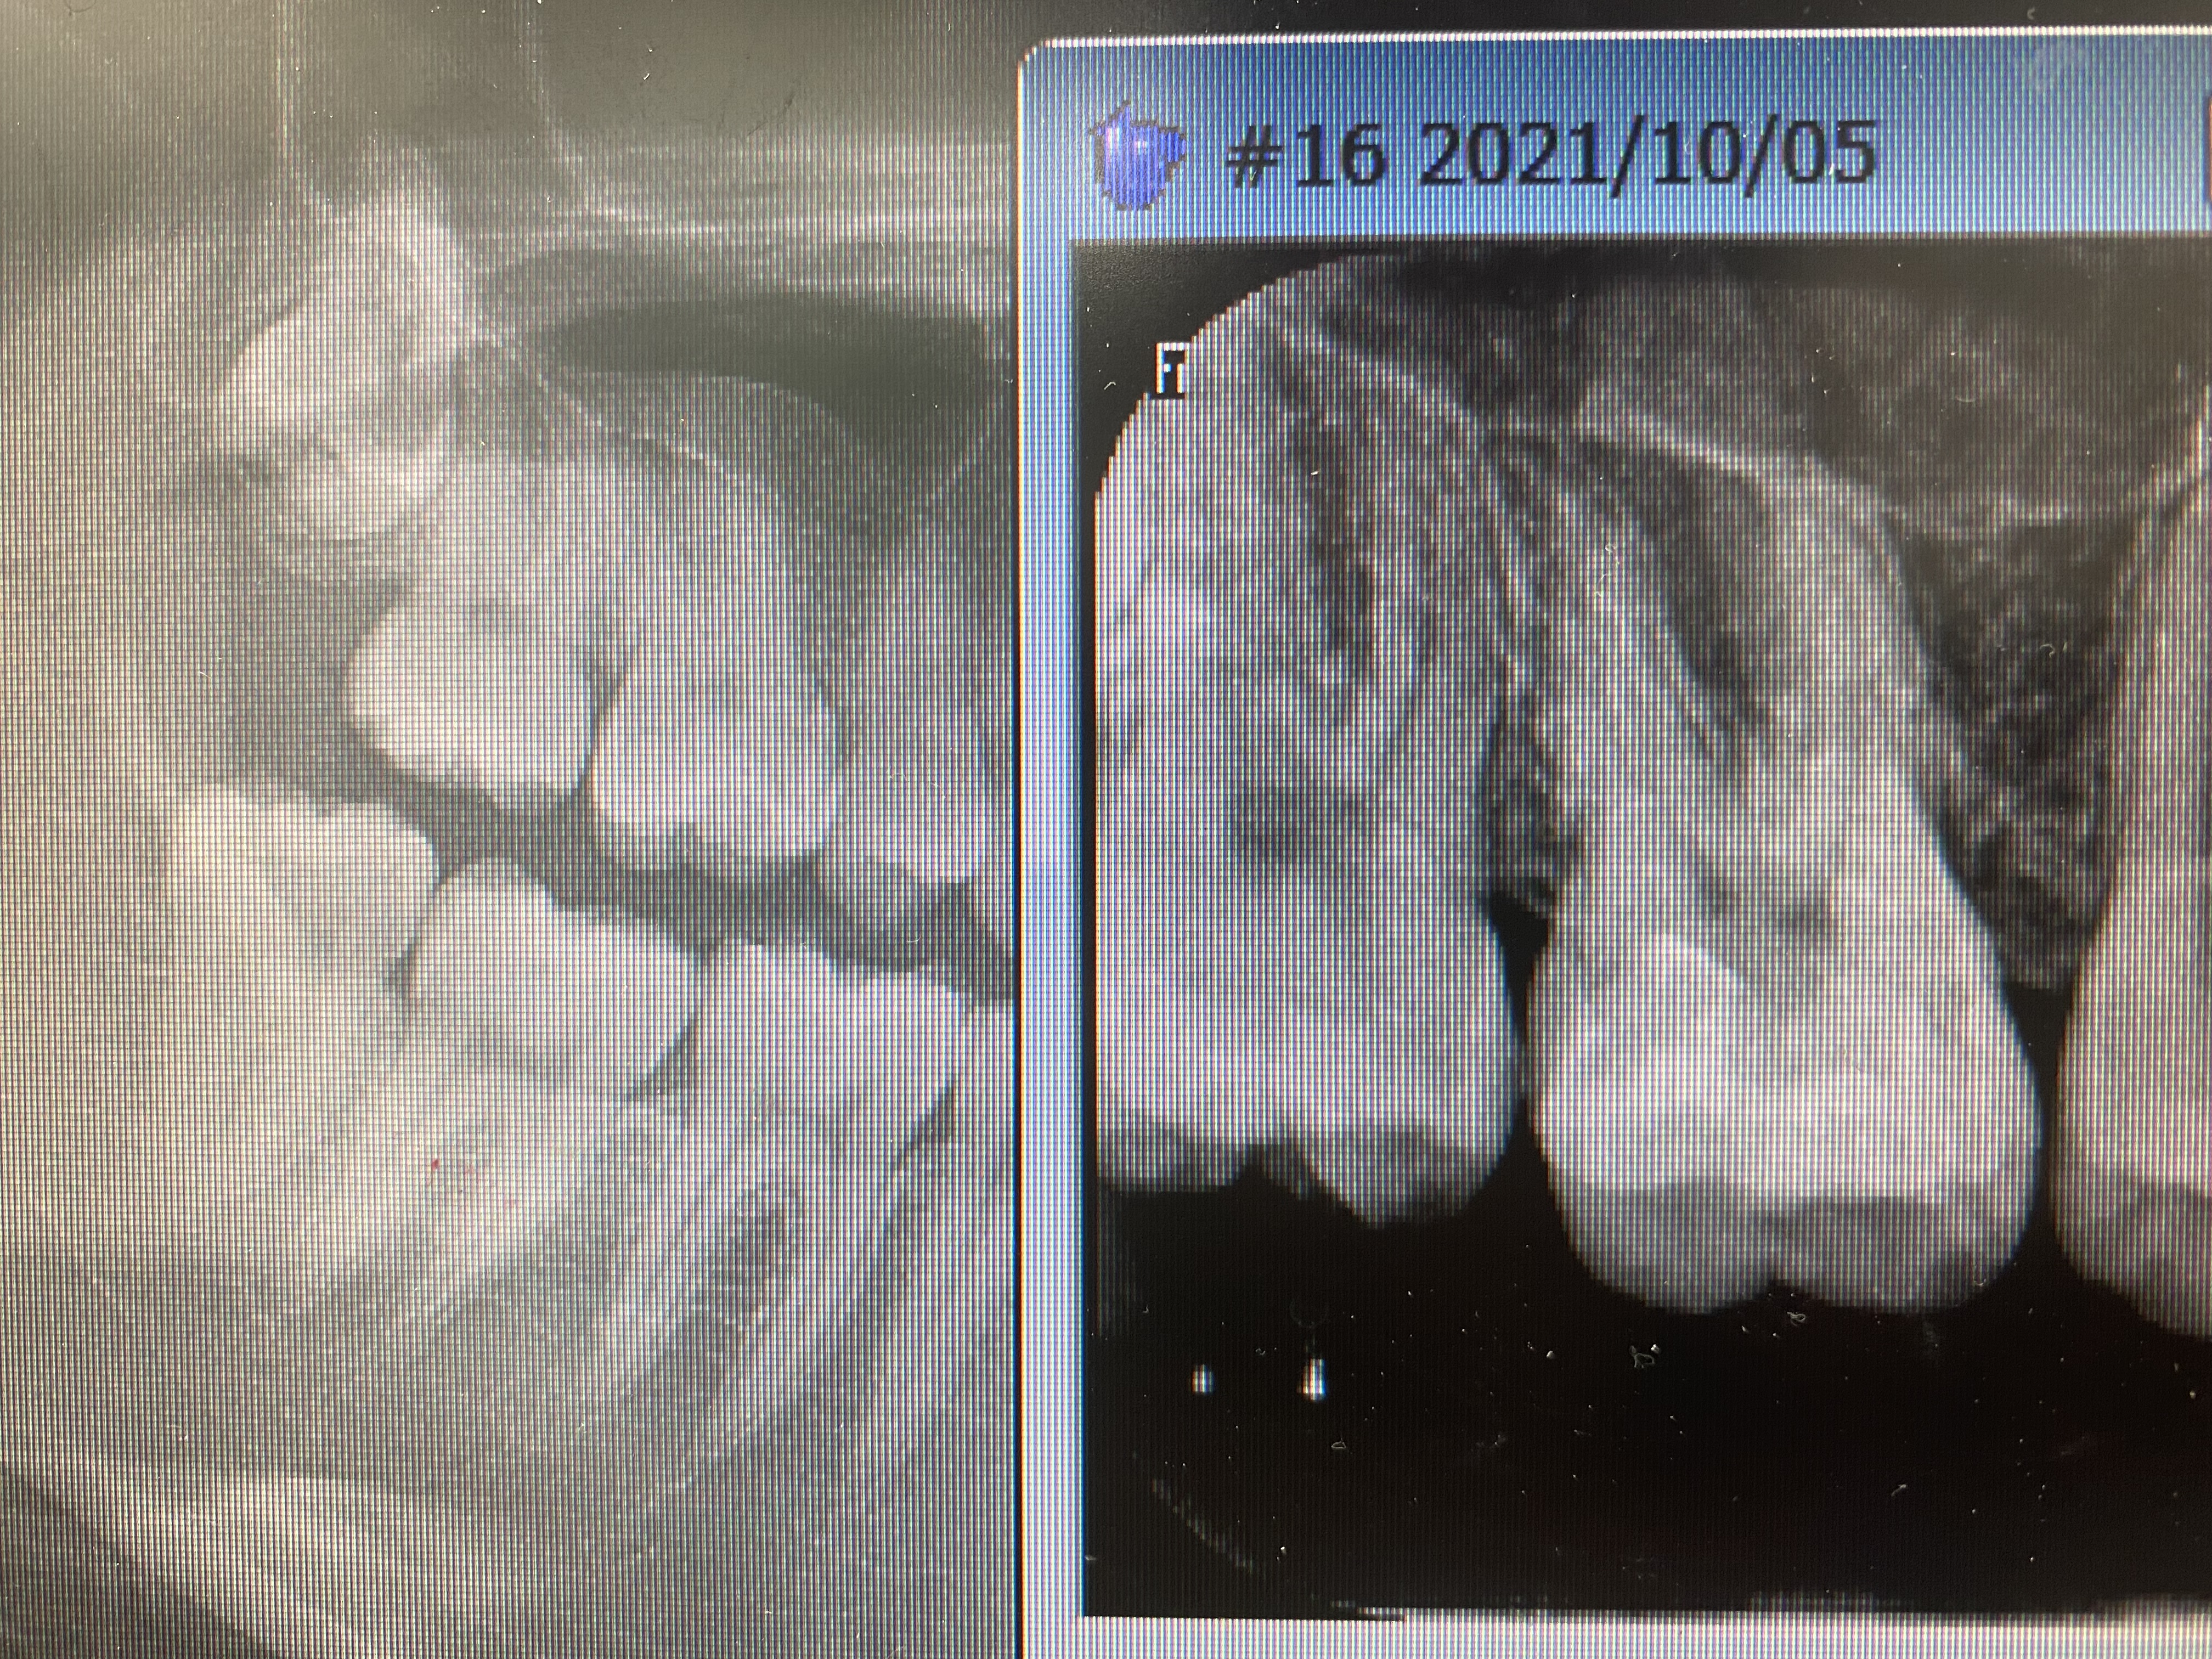

最低限の削除量

2022/03/11ブログ